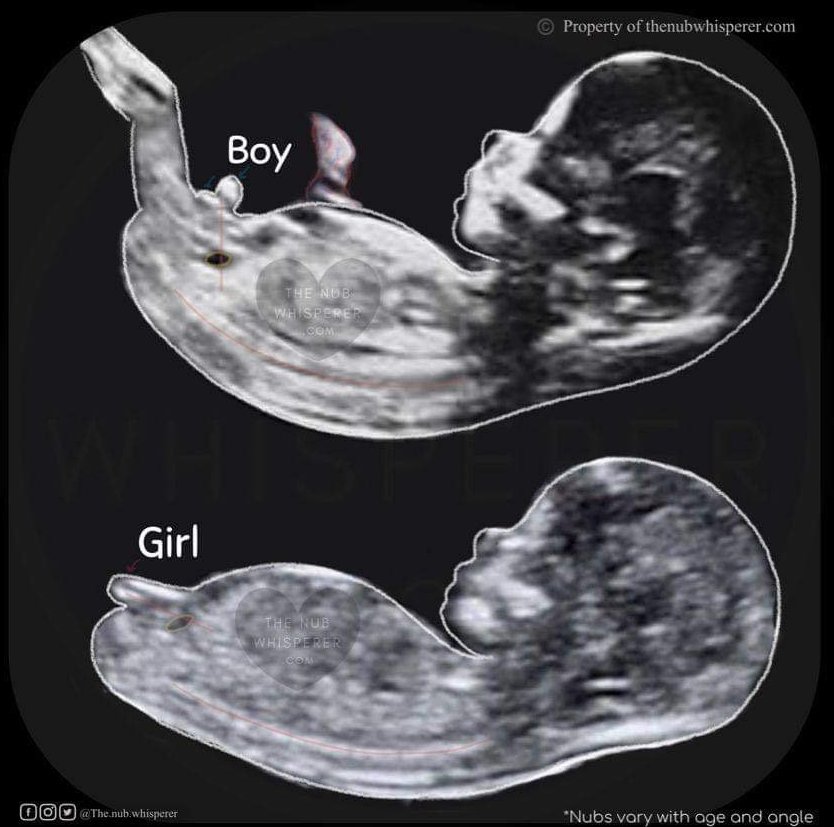

Какви прегледи и изследвания се правят по време на бременност, кога се извършват и какви са техните резултати?

По време на бременност се извършват различни прегледи и изследвания, като ранна фетална морфология (ФМ), биохимичен скрининг (БХС), генетични тестове, цитонмазка, микробиология, урина, глюкоза и други. Тези прегледи имат за цел да проверят здравето на бебето и да открият възможни проблеми. Винаги е добре да се консултирате с вашия лекар относно резултатите от тези прегледи и кои са най-подходящите за вас.

Какво представлява феталната морфология и кога се извършва?

Моята ФМ и БХС са на 22.12. и вече нямам никакво търпение! Стомахът ми се свил от вълнение и притеснение. Не съм била на преглед от 1.12. Тайничко се надявам да разберем пола тогава